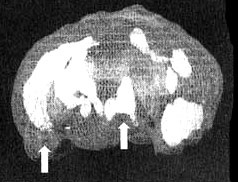

Первая попытка провести Марку это исследование окончилась тем, что он выдернул из руки капельницу и убежал из клиники. Через час он пришел ко мне в кабинет и, бешено ругаясь, вновь обвинил меня в попытках его отравить. Я позвонил его матери, которая успокоила его и сидела с ним рядом все время, пока шло сканирование. Результаты показали значительное снижение активности в левой височной доле.

Мозг Марка. Агрессивность

Трехмерное изображение снизу — активный мозг. Обратите внимание на выражение пониженную активность особенно в левой височной доле (стрелка).